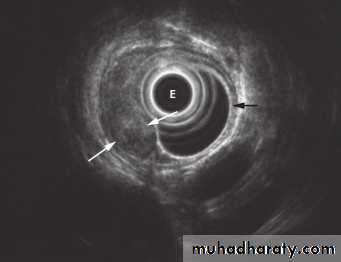

Stricture

Benign vs. malignant Causes Specific locationContrast study EUS CT